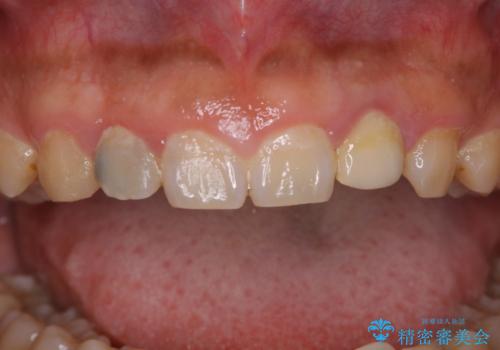

PMTC60分コースを行いました。

20年ぶりのクリーニングということもあり、歯の表面全てにプラークが付着していました。

プラークの細菌によりかなり歯ぐきが腫れていました。1度のクリーニングで汚れは落とせますが、このまま何もしないとまた同じようにプラークが付着し、それを繰り返すことになるだけでなく、歯周病や虫歯が進行してしまいます。そうならないためには、日々のケア、ホームケアがとても大事になっていきます。